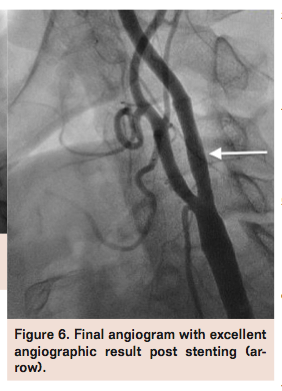

(Figure 3). An Xact 7-9 mm x 40 mm self-expanding stent (Abbott Vascular) was deployed in the left ICA extending into the CCA (Figure 4), and postdilated using a Viatrac 5 mm x 30 mm balloon (Abbott Vascular) with good expansion (Figure 5). Aspiration of debris was performed prior to deflating both the left ECA and CCA balloons. The ECA balloon wire and Prowater guidewires were withdrawn, and final angiograms confirmed excellent angiographic results with brisk flow through the left ICA (Figure 6) and preserved intracerebral flow. The patient was transferred to the intensive care unit for observation overnight and discharged home the following day on dual-antiplatelet therapy without any complications.